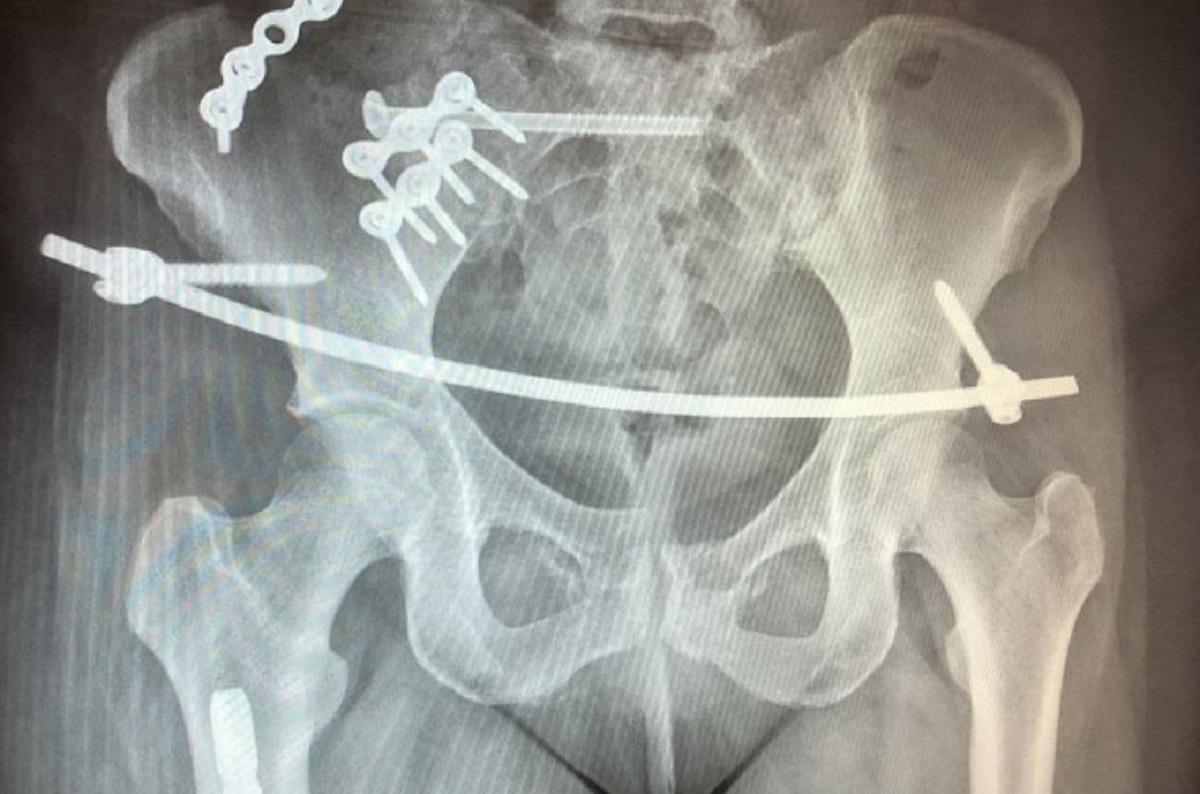

Mărturia a unei mame de 42 de ani, care a supravieţuit unui teribil accident de maşină: „Nu puteam să respir”

O mamă de 42 de ani a trecut pe lângă moarte, dar a supravieţuit